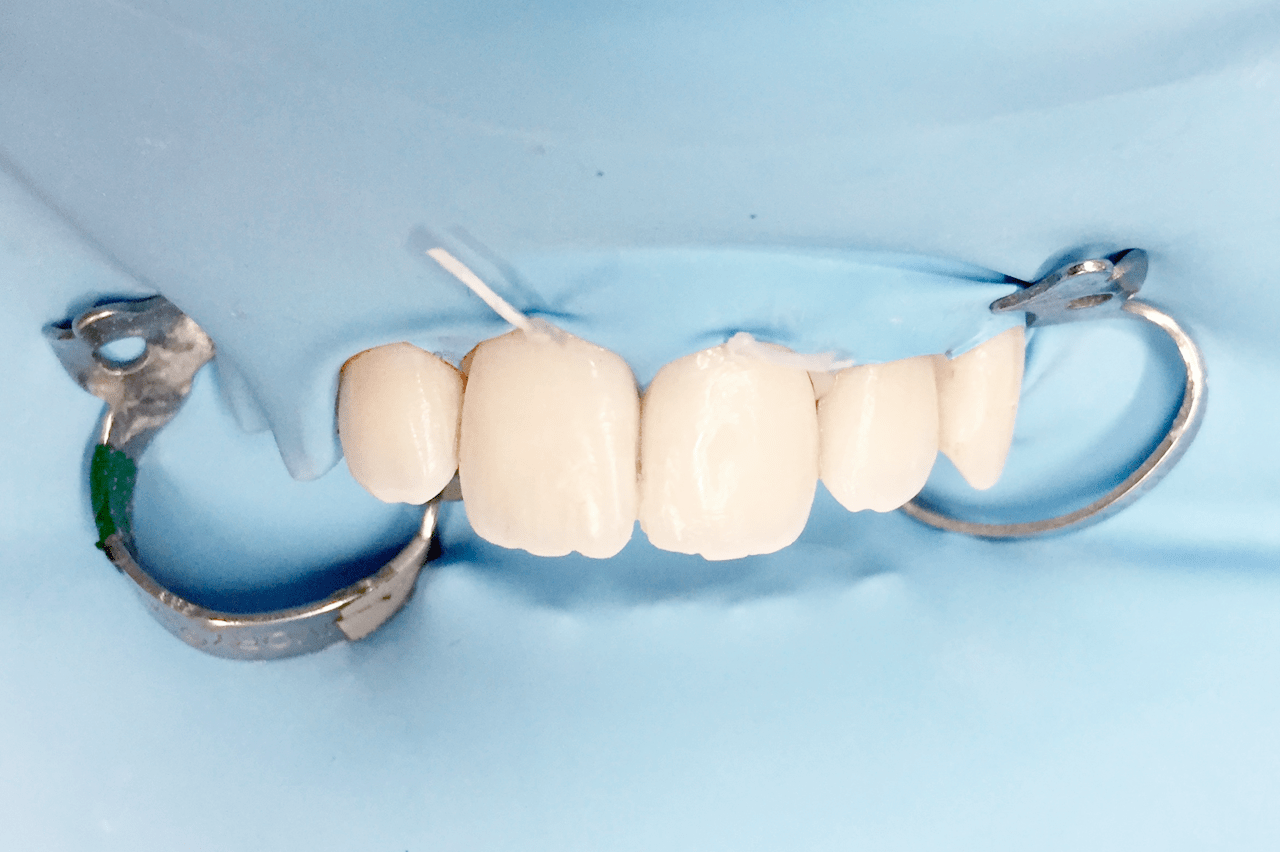

Conservativa

La conservativa è la branca dell'odontoiatria che si occupa del restauro di denti vitali danneggiati da perdite di sostanza (smalto e dentina) causate da eventi traumatici o da processi cariosi.

Presso i nostri studi utilizziamo solo materiali compositi che permettono di eseguire otturazioni estetiche assolutamente invisibili e durature nel tempo.